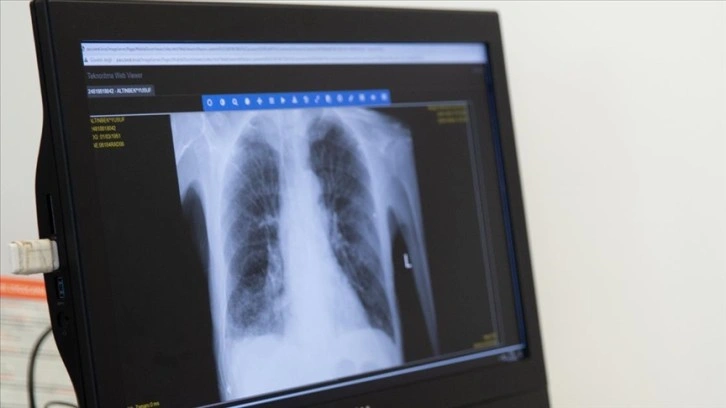

Üçüncü el sigara maruziyeti 40 yaş altında KOAH gelişmesine yol açabiliyor

Sigara kullananların giydiği kıyafetlere sinen partiküllerin, ortamda bulunan kişiler tarafından solunması olarak ifade edilen "üçüncü el sigara maruziyeti"nin, 40 yaş altında KOAH'ın hasta gelişmesine yol açabildiği uyarısında bulunuldu.

Ankara Şehir Hastanesi Göğüs Hastalıkları Kliniği Eğitim Görevlisi Prof. Dr. Hatice Kılıç, AA muhabirine yaptığı açıklamada, KOAH'ın genellikle öksürük ve balgam çıkarılması, nefes darlığı ile karakterize, yaygın, önlenebilir ve tedavi edilebilir bir hastalık olduğunu söyledi.

KOAH'ın endüstrileşmenin yanı sıra modern yaşamda hareketsizliğin artmasıyla giderek artan küresel bir halk sağlığı sorunu olduğunu ifade eden Kılıç, "Dünyada her 10 kişiden birinin, Türkiye'de ise her 5-6 kişiden birinin KOAH olduğu bilinmektedir. Ayrıca dünyada ve ülkemizde inme, kalp hastalıklarından sonra 3. sıradaki ölüm nedenidir." bilgisini verdi.

Kılıç, KOAH'ın, genetik özelliklerin sigara ve hava kirliliği gibi çevresel faktörlerden etkilenerek zaman içinde ortaya çıktığını, risk faktörlerinin hangi ağırlıkta ortaya çıkacağının da kişiden kişiye değiştiğini anlattı.